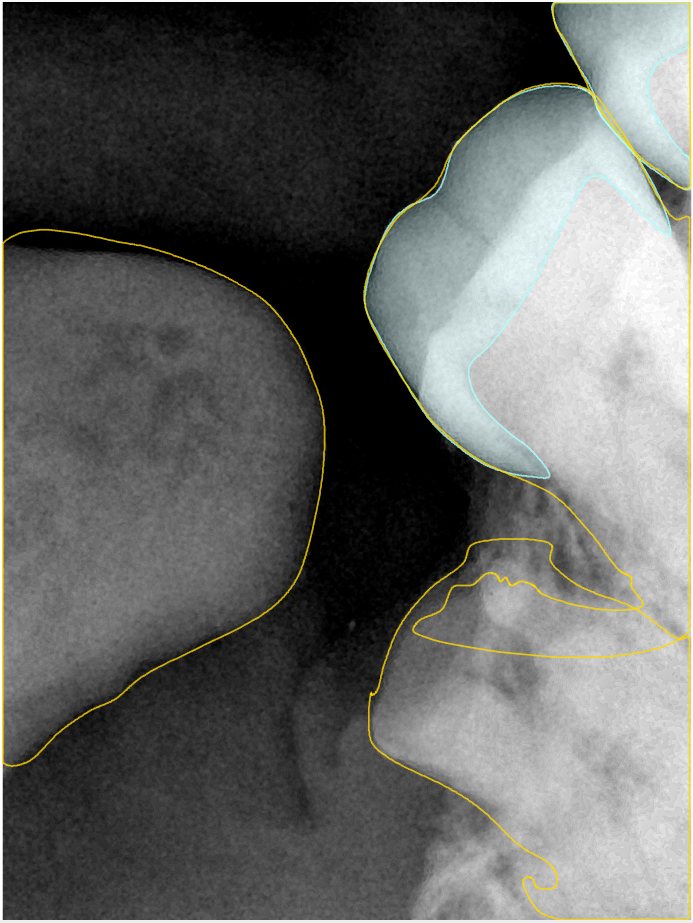

CR/DR 牙齿分割阶段记录

当前进展

- 完成了 CR/DR 牙齿相关分割训练

- 当前结果已经达到阶段预期,但仍有细节问题需要继续处理

相关测试

遇到的问题

- 训练过程中出现过 mask 下移问题

- 部分结果会出现 box 填充异常

- mask 边缘仍然有比较明显的锯齿感

参考

第二版算法问题测试